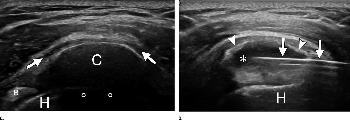

Figure 3. US images show supraspinatus calcification in a 29-year-old woman. (a) Calcific deposit (C) can be clearly seen with moderate acoustic shadowing (circles). Subacromial bursitis (arrows) can be seen. (b) End of treatment. Most calcific material was removed from calcification (∗) with single-needle procedure. Only a thin calcific wall (arrowheads) was left. Needle (arrows) is still inside calcification. B = biceps tendon, H = humeral head.